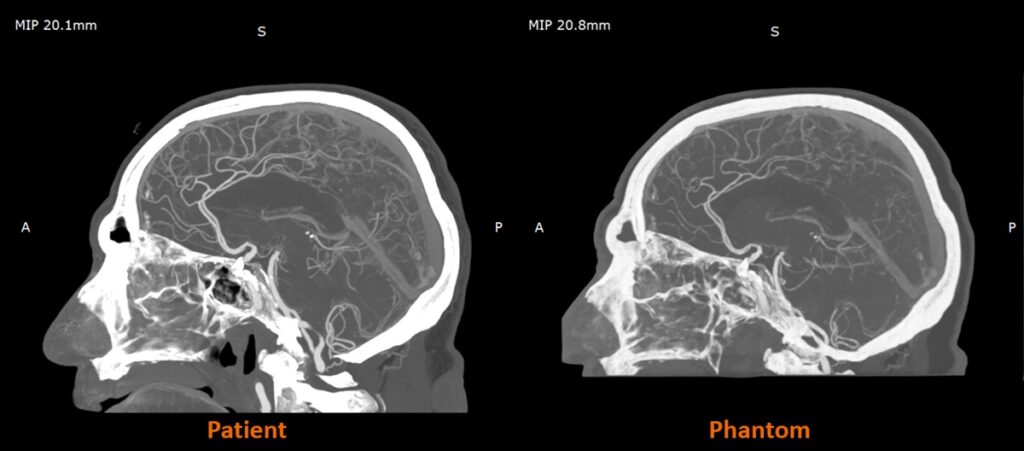

UK-based work with partners such as CPI and Beaumont Hospital is already demonstrating the impact of radiopaque 3D-printed models in practice, with radio-realistic cerebral angiography phantoms being used to improve the fidelity of imaging-based training and create more controlled, repeatable environments for research.

Early research from the Stratasys–Siemens Healthineers collaboration shows that 3D printed RadioMatrix™ phantoms can closely replicate real human tissue in CT imaging, with deviations reported as low as single Hounsfield units (HU) in critical areas such as grey matter and veins. By combining Stratasys’ Digital Anatomy™ 3D printing technology and radiopaque materials with advanced imaging algorithms, the partners are demonstrating anatomically realistic, radio-accurate phantoms that preserve fine anatomical details and pathological variations while offering a more consistent, ethical alternative to cadavers. These models are expected to improve how radiologists validate and optimize CT protocols and accelerate the development of new imaging algorithms for more precise diagnosis and treatment planning.